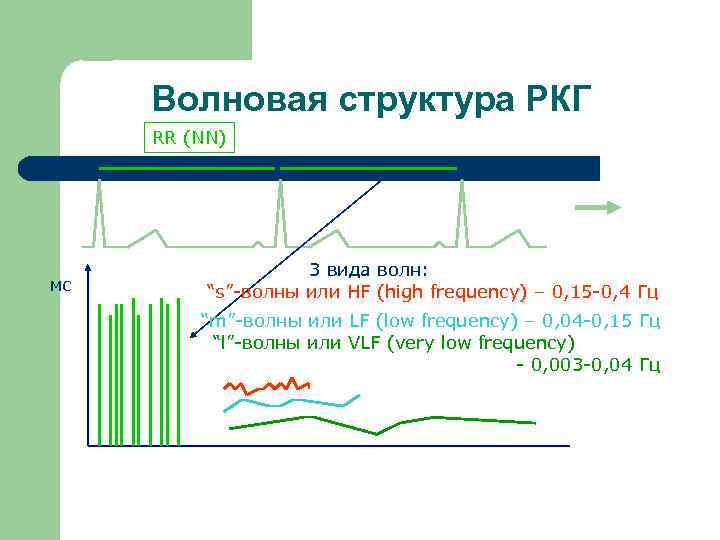

Волновая структура РКГ RR (NN) мс 3 вида волн: “s”-волны или HF (high frequency) – 0, 15 -0, 4 Гц “m”-волны или LF (low frequency) – 0, 04 -0, 15 Гц “l”-волны или VLF (very low frequency) - 0, 003 -0, 04 Гц